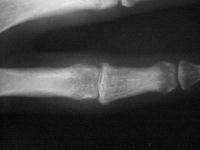

Xrays show an apparently healed PIP fracture dislocation with dorsal subluxation - but concentric tracking of the abnormal palmar articulation.